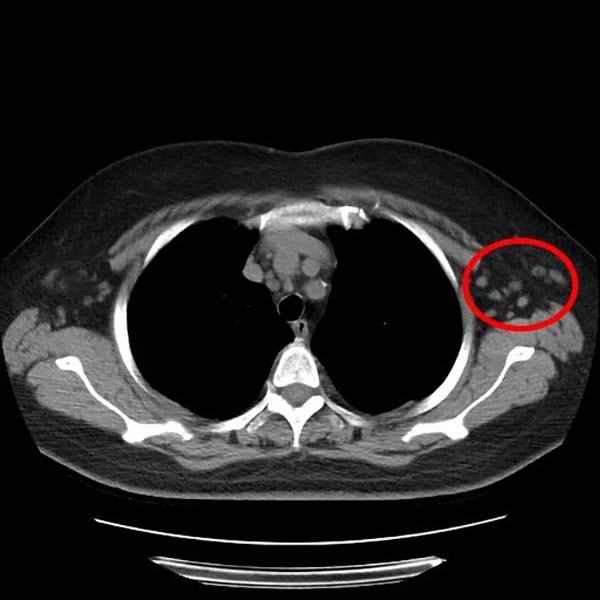

来到清华大学附属垂杨柳医院感染性疾病科后,副主任医师王同德接诊了该患者,并完善了相关检查,初步结果提示其血尿化验基本正常,流感及新冠抗原检测为阴性,胸部CT未见肺炎表现,但影像提示左侧腋窝淋巴结肿大。

▲红圈处可见肿大淋巴结